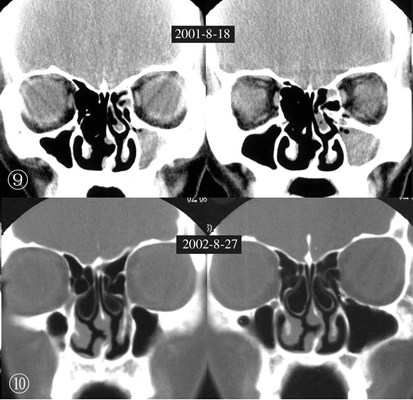

鼻中隔偏曲圖片

鼻中隔彎曲手術圖解 (9)